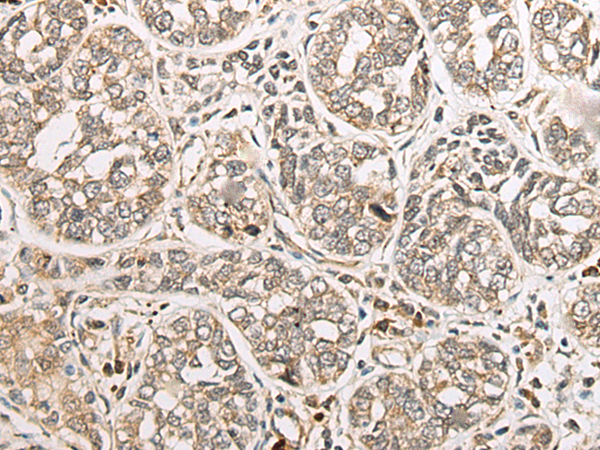

分类: 科研抗体货号: P09429别名: CLSP应用: IHC反应种属: Human